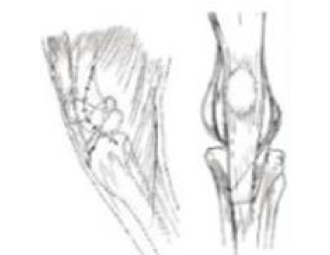

무릎 및 십자인대수술

TPLO : Tibial Plateau Leveling Osteotomy

강아지 후지파행의 한 원인인 전십자인대 단열의 경우에 시행하는 수술로서 최근 낭외재건술보다 우선 선택되는 수술법입니다.

강아지 무릎뼈탈구(슬개골탈구) 교정 수술

활차구 성형술

대퇴근막 중첩술

경골결절 변위술

경골회전방지&자봉합